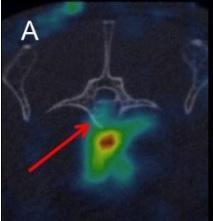

Les chercheurs testent ici une combinaison de cellules souches mésenchymateuses (dérivées de la moelle osseuse), provenant d’adultes et l’hormone parathyroïde (PTH) sur l’animal. Chez l’Homme, l’hormone PTH régule le taux de calcium et assure donc une fonction essentielle dans la santé et la solidité des os. Durant 21 jours, les animaux de laboratoire (rats et porcs), présentant des fractures vertébrales ont reçu des injections quotidiennes de PTH et, durant cette même période, 5 injections de cellules souches. L’effet thérapeutique de la combinaison cellules souches-PTH a été comparé aux résultats de la  thérapie par cellules souches seule, des injections de PTH seule, et à l’absence de traitement. La régénération osseuse a été contrôlée à plusieurs reprises par scanner.

thérapie par cellules souches seule, des injections de PTH seule, et à l’absence de traitement. La régénération osseuse a été contrôlée à plusieurs reprises par scanner.

L’étude montre qu’à la fois les cellules souches et l’hormone ont un effet bénéfique sur le processus de guérison des fractures : la migration des cellules souches vers la zone de fracture de l’os est accélérée et la formation osseuse augmentée. Mais l’étude montre que la combinaison cellules souches et PTH démultiplie ces effets, permet d’augmenter de façon encore plus significative la formation d’os –multipliée par 3 ou 4, vs chaque thérapie solo- et finalement accélère le processus de cicatrisation de ces fractures osseuses causées par l’ostéoporose.